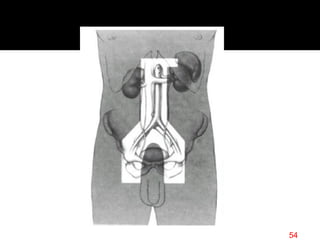

Mantle

bilateral cervical,

SCV, infraclavicular,

mediastinal, hilar,

and axilla

Mini-mantle:

mantle without

mediastinum, hila

Modified mantle:

mantle without axilla

55

mini mantle modified mantle